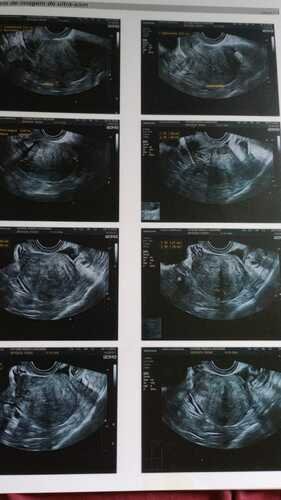

Já tentei 03 vezes o pedido da realização da cirurgia, que foi negada pelo SUS. Então, juntei recursos e fui consultar com um especialista particular, Dr Igor Chiminácio, na cidade de Pato Branco-PR. Este médico afirmou ser possível a realização da cirurgia, será muito delicada, pois é preciso ser retirado o meu útero, os dois ovários, apêndice, parte do meu umbigo e descolar o mesmo do intestino, pois esta todo aderido, inclusive o meu nervo ciático esta prejudicado em decorrência dessas aderências. Estou aguardando a autorização de uma ressonância pra saber se será necessário a retirada de parte do intestino.